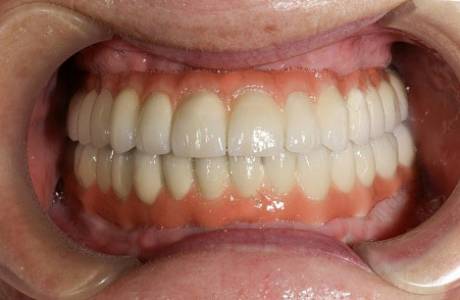

До лечения

Пациентка обратилась с жалобами на отсутствие зубов на верхней и нижней челюсти, снижение высоты нижнего отдела лица, невозможность носить съемные протезы. Принято решение об установке имплантов на обе челюсти с предварительными синус лифтингами и остеопластикой.

После лечения

По прошествии срока приживания имплантов были изготовлены металлокерамические коронки, основываясь на заданной форме и высоте временных коронок. Пациентка очень довольна результатом.